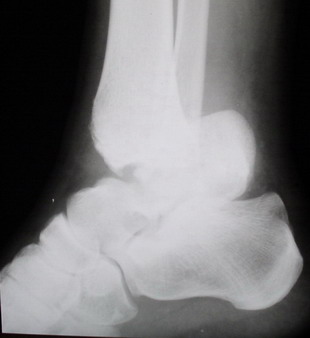

Среди повреждений таранной кости (Hawkins III-IV) с одновременной травмой лодыжек встретилось следующее (см. вложение). Пациент упал в колодец на глубину 10 метров (Х.2002 г.), госпитализирован с диагнозом: з/перелом шейки правой таранной кости (Hawkins IV) с переломовывихом тела назад и кнутри, закрытый перелом внутренней лодыжки и переднего края большеберцовой кости. Оперирован в первые 12 часов после травмы, выполнена открытая репозиция таранной кости, внутренним и передне-внутренними доступами, остеосинтез переломов шейки и тела губчатыми винтами, для реваскуляризации тела таранной кости первичный компрессионный над- и подтаранный артродез. Синтез внутренней лодыжки губчатым винтом. Удаление винтов через 1 год,2 мес. Получен анкилоз указанных суставов с сохранением длины конечности, полная реваскуляризация таранной кости, о чем говорит сращение ее переломов, отсутствие отеков и

цианоза стопы и голени. Компенсаторная подвижность переднего и среднего отделов стопы около 15-20 градусов за счет поперечного (Шопара) сустава стопы. Считаю оправданной подобную тактику, не смотря на угрожаемый прогноз (100% асептический некроз) по классифицкации Hawkins.